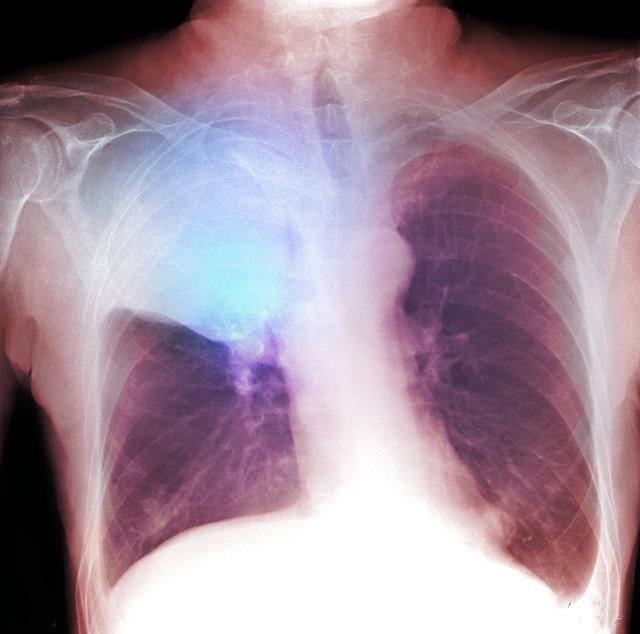

肺类癌属于少见性肿瘤,约占肺部肿瘤的1%-2%,占全部类癌的10.2%~11.5%,分中央型类癌和周围型类癌两种。肺类癌起源于支气管肺粘膜及粘膜下腺体的嗜银细胞,即Kulchitsky细胞。这些细胞浆内有神经内分泌颗粒,具有分泌功能。由于类癌属于神经内分泌肿瘤,有些文献报道部分类癌可以出现类癌综合症症状,表现为阵发性皮肤潮红、腹泻、哮喘、心动过速、面部充血、血压波动和紫绀,但出现此症状的病例较少,病人也可出现非特征性症状,例如胸痛、发热。

据报道,类癌患者的年龄幅度较大,可从10岁~83岁,中位年龄为45岁。临床根据类癌的生物学行为分为:分化较好的典型类癌和有侵袭性的不典型类癌,典型类癌占多数,非典型类癌仅占11.4%。典型性类癌预后较好,即使伴有同侧纵隔淋巴结转移,5、10和15年生存率分别为92%、88%、76%,而侵袭性不典型类癌的预后较差,5年和10年生存率分别为69%和24%~52%。预后与临床分期及淋巴结转移相关。典型类癌的平均年龄比非典型类癌要年轻10岁,而且它是儿童期最常见的肺部恶性肿瘤。类癌中央型多于周围性,这是因为越靠近中心支气管,粘膜内的K细胞分布越多,发生类癌的机会越大。

CT上肺类癌较其他肺癌钙化更常见,在组织学上肺类癌钙化的发生率约为30%,中心型类癌可高达39%。肺类癌转移少见,中央型肺类癌病程长,进展缓慢,倍增时间长,预后相对较好。支气管镜及活检病理对肺类癌的确诊率低,需要进一步免疫组化检测综合判断。对疑似类癌综合征的患者进行24h尿5-羟吲哚(5-HIAA)水平测定,如5-HIAA升高对类癌诊断有一定帮助。由于典型肺类癌预后较好,术后一般不考虑化疗。对于非典型类癌,5年和10年生存率比较低,不管有没有淋巴结的转移,目前还是推荐术后化疗。由于对化疗的敏感性较低,晚期患者化疗有效率不高。